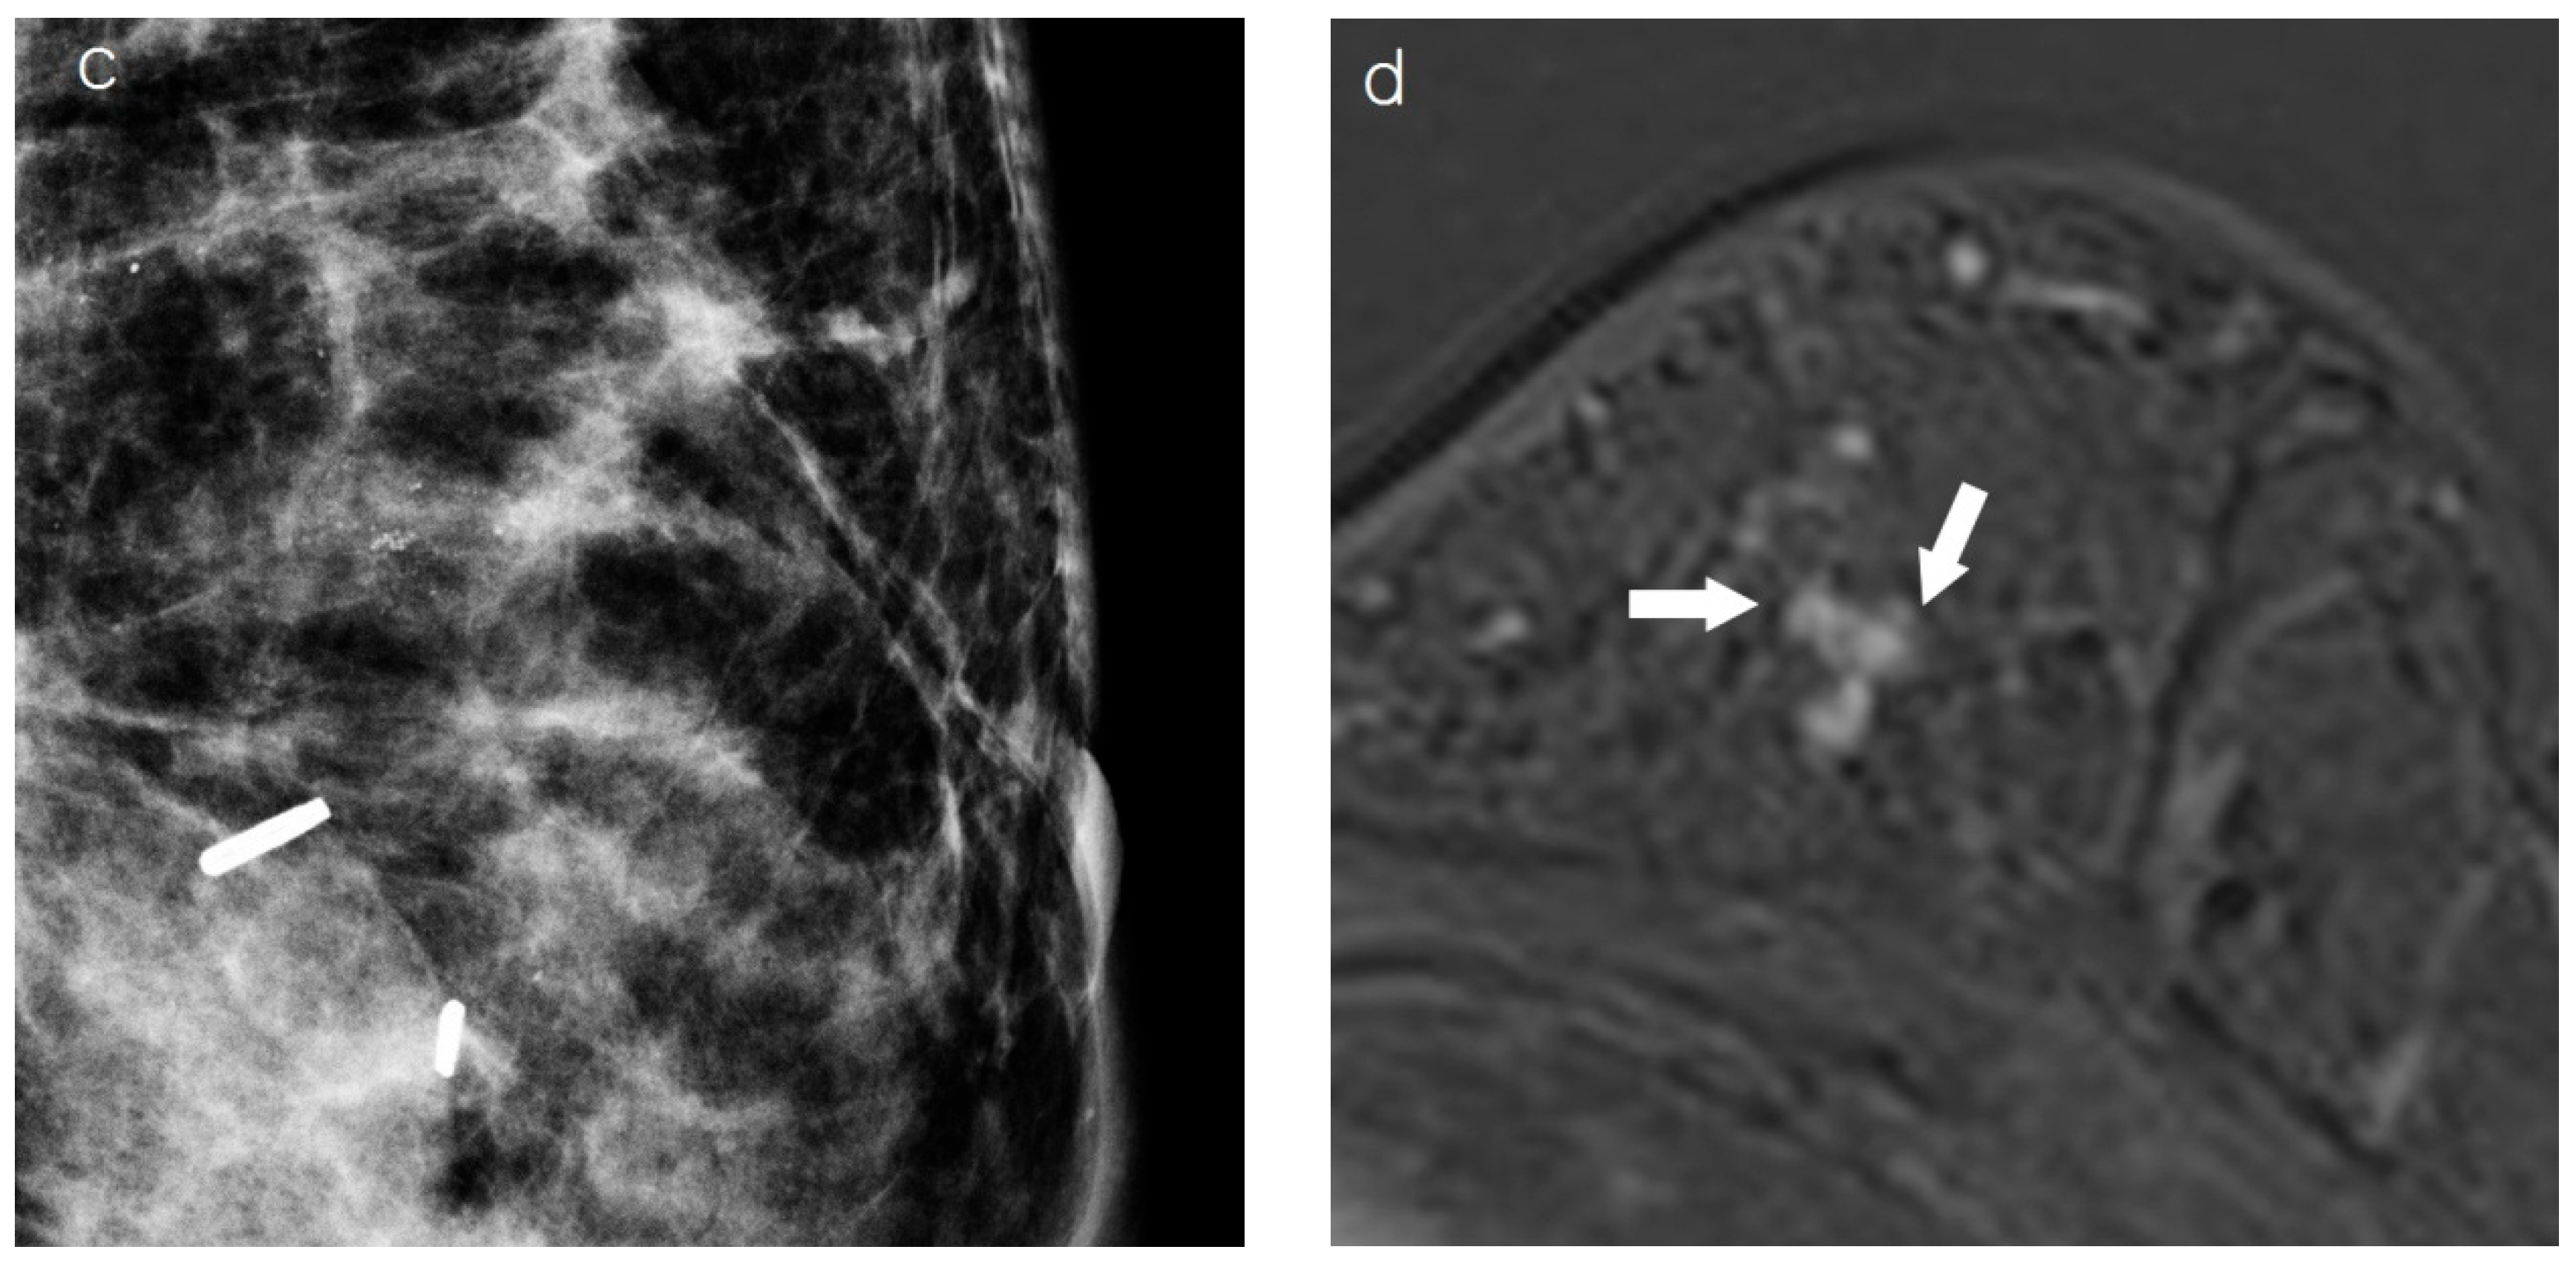

2.3. Assessment of Breast Cancer on Chest CT

2.4. Imaging Analysis

| Mass | <0.001 | |||

| None | 35 (51.5) | 24 (92.3) | 11 (26.2) | |

| Yes | 33 (48.5) | 2 (7.7) | 31 (73.8) | |

| Tumor presentation | 0.002 | |||

| Mass | 48 (68.6) | 7 (38.9) | 41 (78.8) | |

| Non-mass | 22 (31.4) | 11 (61.1) | 11 (21.2) | |